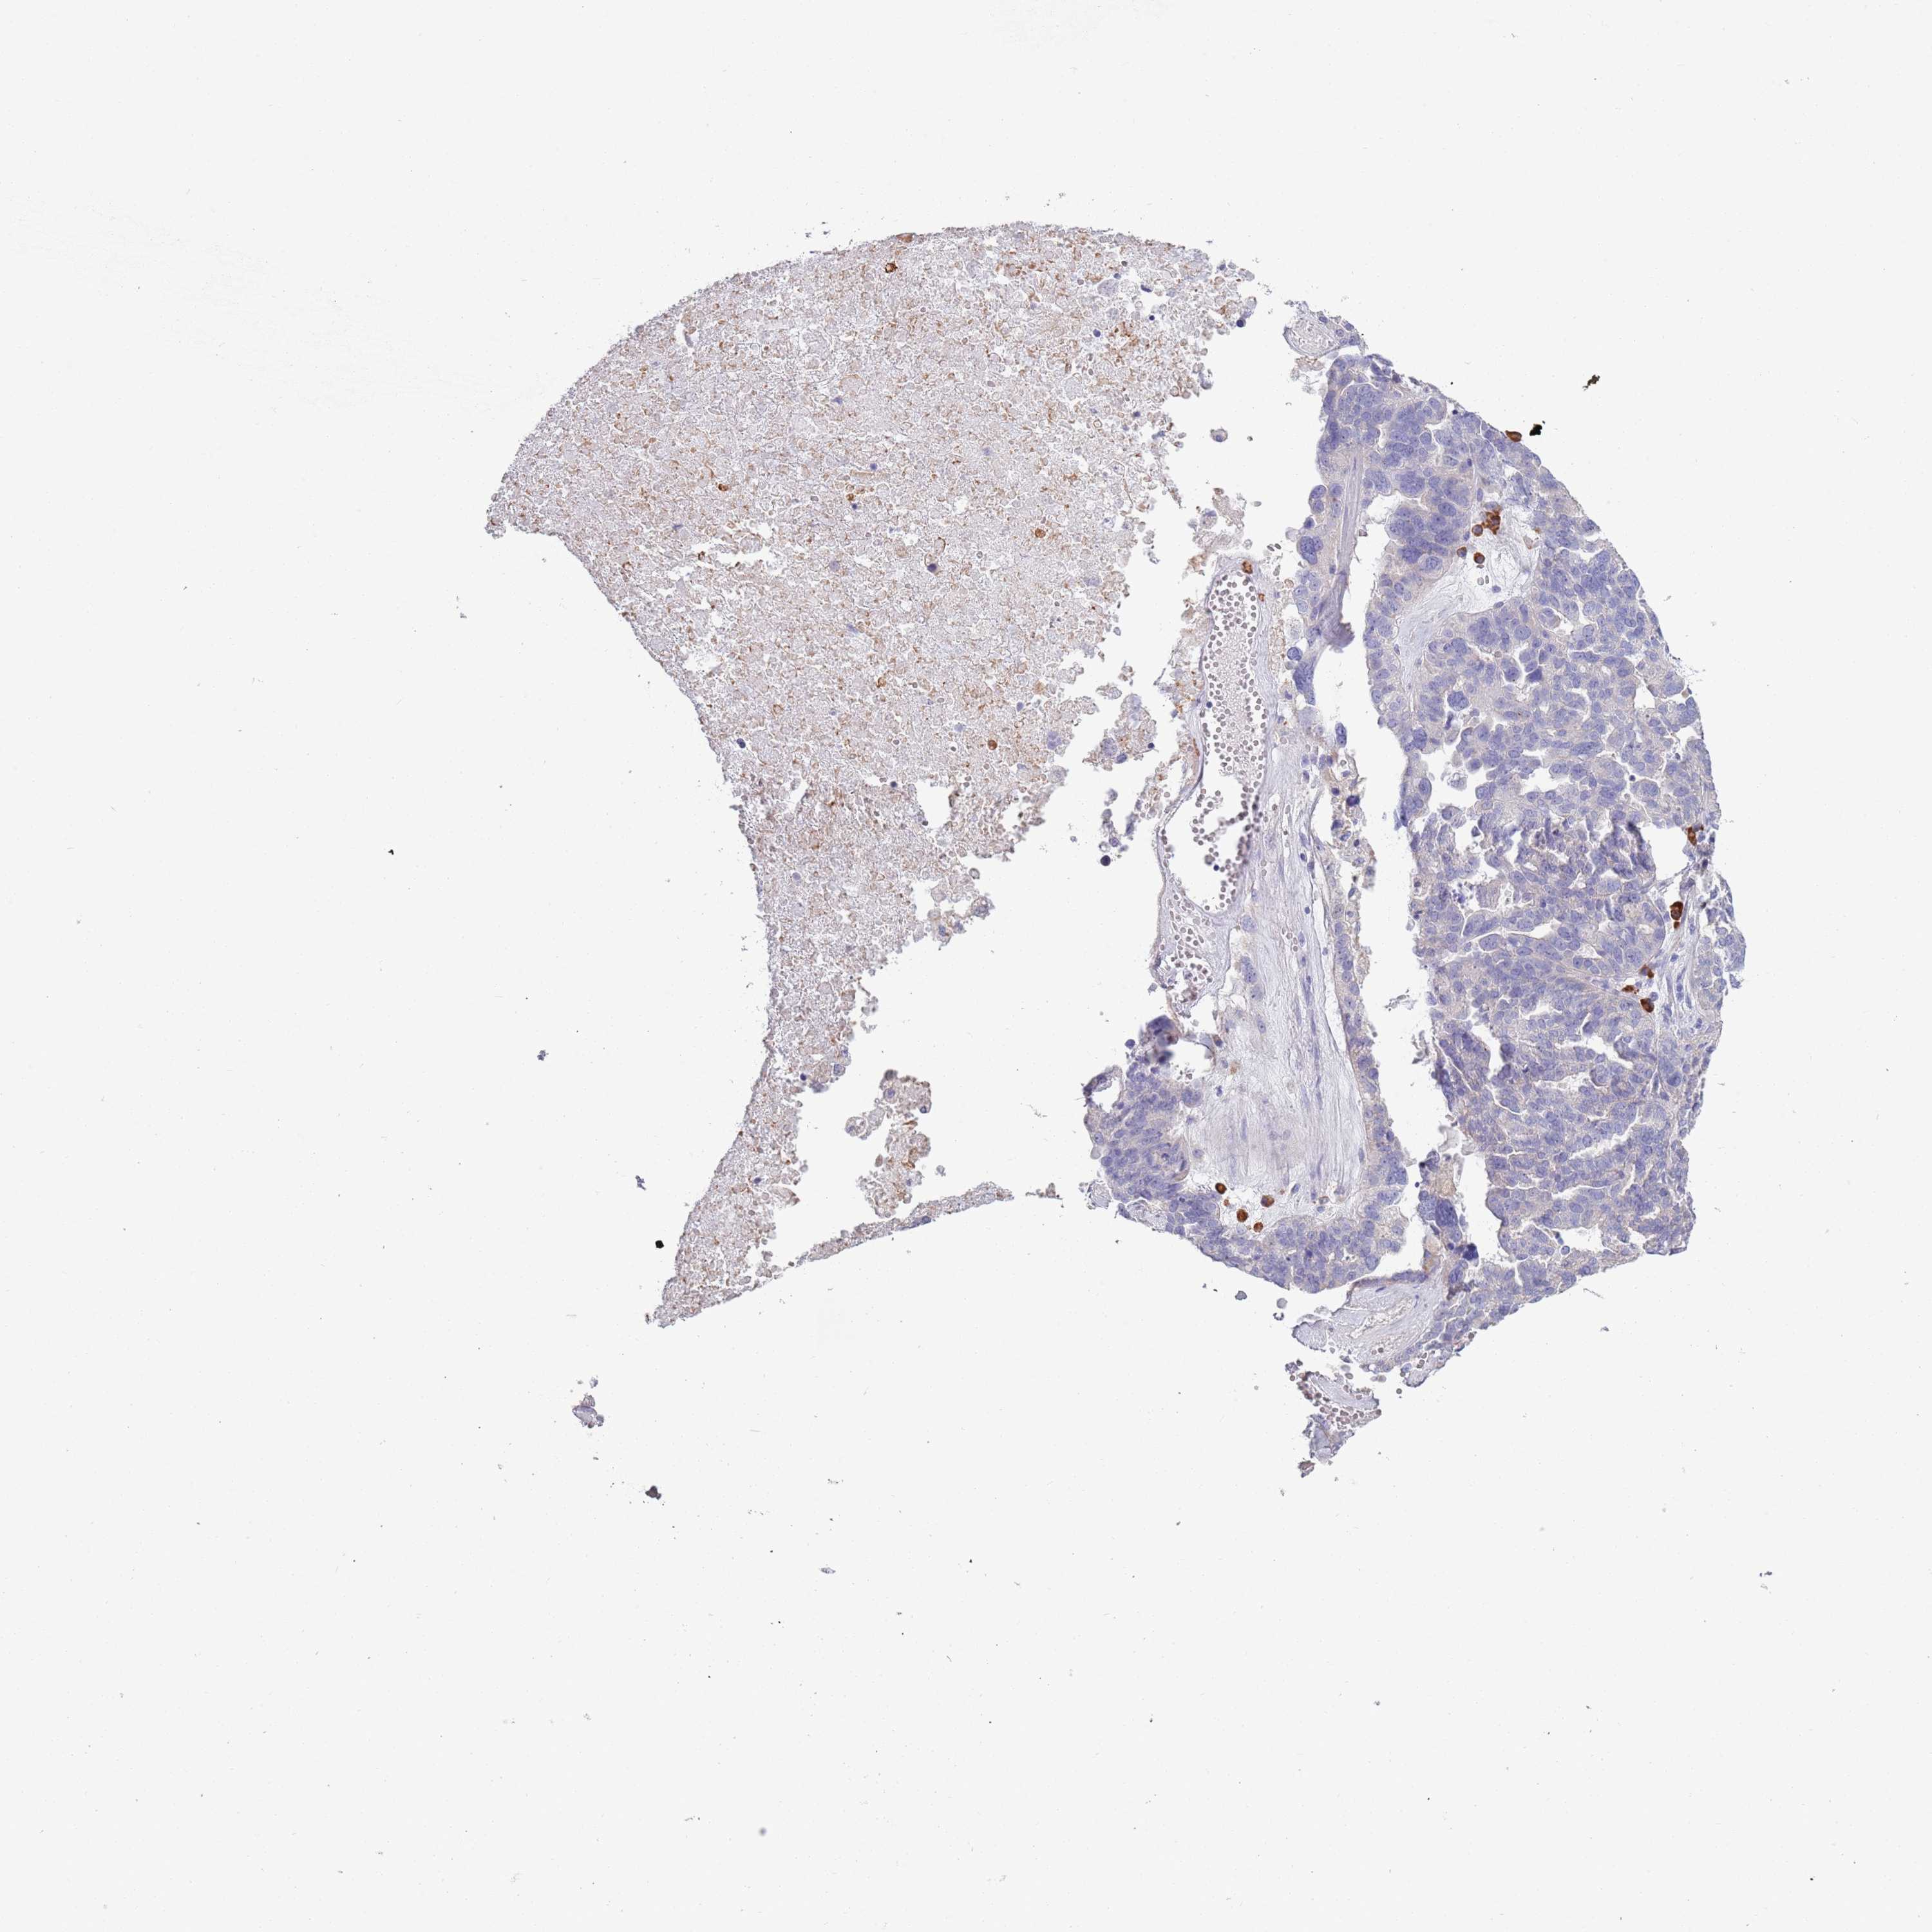

OVARIAN CANCER - Protein expressioni

A mouse-over function shows sample information and annotation data. Click on an image to view it in a full screen mode. Samples can be filtered based on level of antibody staining by selecting one or several of the following categories: high, medium, low and not detected. The assay and annotation is described here.

Note that samples used for immunohistochemistry by the Human Protein Atlas do not correspond to samples in the TCGA dataset.

Antibody stainingi

Antibody staining in the annotated cell types in the current human tissue is reported as not detected, low, medium, or high, based on conventional immunohistochemistry profiling in selected tissues. This score is based on the combination of the staining intensity and fraction of stained cells.

Each image is clickable and will lead to virtual microscopy that enables deeper exploration of all samples and also displays staining intensity scores, fraction scores and subcellular localization as well as patient and tissue information for each sample.

Antibody HPA048884

Staining

High

Medium

Low

Not detected

Intensity

Strong

Moderate

Weak

Negative

Quantity

>75%

75%-25%

<25%

None

Location

Nuclear

Cytoplasmic/membranous

Cytoplasmic/membranous,nuclear

Cystadenocarcinoma, serous, NOS

Carcinoma, NOS

Cystadenocarcinoma, mucinous, NOS

Carcinoma, endometroid